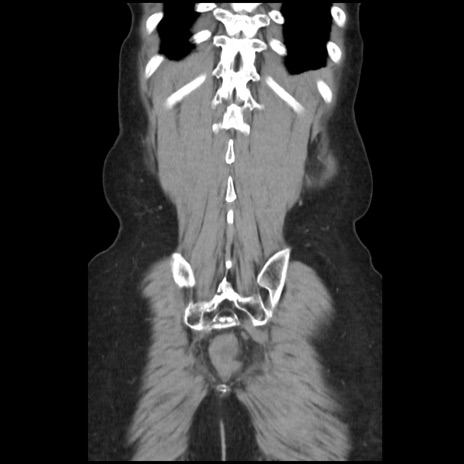

矢状断像